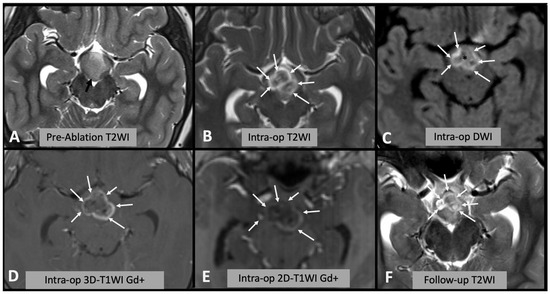

Figure 1. (A) Axial T2WI showing the appearances of the hypothalamic hamartoma before laser ablation (black arrow). (B) Intra-operative axial T2WI immediately after laser ablation, showing marked T2WI hyperintense oedema within the hamartoma (white arrows). (C) Intra-operative axial DWI after laser ablation showing hyperintense rim (white arrows) surrounding a hypointense core (asterisk). (D,E) Post-contrast T1WI sequences showing enhancing rim within the hamartoma (arrows); after injection of contrast it is not possible to repeat laser ablation; thus, this sequence is not useful for intra-operative decision making. Note the differences between (D) spin-echo 2D T1WI and (E) 3D “MPRAGE” T1WI; in the latter, the rim is less evident due to technical differences. (F) Follow-up axial T2WI showing the encephalomalacic area of permanent damage.

We assessed the area of signal change on T2WI, DWI (both rim of diffusion restriction and internal hypointense core) and rim of contrast enhancement on T1WI as a percentage of the area of the whole hamartoma and compared the results with the encephalomalacia (fluid area on T2WI on follow-up scan) as a percentage of the whole hamartoma on follow-up (Figure 1). Where residual disconnected tissue was present within the encephalomalacic area, it was considered together with it, as the disconnected tissue is no longer active (Figure 2).

Of note a “core” of hypointensity was sometimes noted on T2WI (Figure 1) but was not visualized in all cases and was much more inhomogeneous than the DWI core, jeopardizing reproducible measurements.

The non-enhancing core in T1WI was also measured and corresponded to the DWI hypointensity core; however, because after contrast is given, it is not possible to repeat the ablation, this sequence is not useful in the intra-operative decision making.